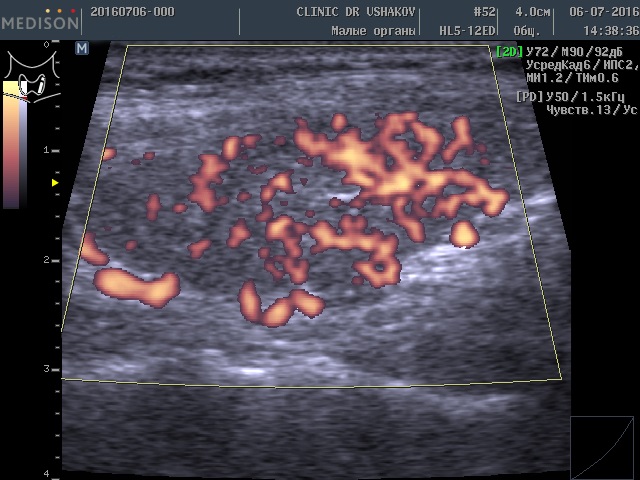

После 2-го курса лечения в «Клинике щитовидной железы» доктора А.В. Ушакова состояние гормонального обмена и самой щитовидной железы значительно улучшилось. Контрольный анализ крови показал (03.11.2016): ТТГ 5,76 мЕд/л (0,4-4,0), Т4св. 11,4 пмоль/л (9-22), Т3св. 4,0 пмоль/л (2,6-5,7), Т4общ. 89,2 нмоль/л (55-137). Как видите, восстановилось количество щитовидных гормонов, а стимуляция щитовидной железы существенно уменьшилась.

При контрольном УЗИ выявлена оптимизация объёма щитовидной железы. Уменьшился до 9 мл (оптимальный объём ЩЖ для этой пациентки 7-8 мл). При этом улучшилась состояние ткани (стал меньше признак лимфоцитарной инфильтрации ― распространённая гипоэхогенность (на снимке ― затемнение фона)). Заметно уменьшилась активность кровотока (рис. 7 и 8).

Рисунки 7 и 8. Пациентка К., 45 лет, левая и правая доли щитовидной железы в режиме ЭДК. После двух лечебных курсов, проведенных в Клинике доктора А.В. Ушакова. Кровоток (обозначен красным цветом) в умеренной и малой степени усилен.

Рисунки 9 и 10. Пациентка К., 45 лет, левая и правая доли щитовидной железы в режиме ЭДК. После трёх лечебных курсов и 5-ти месячного перерыва (пациентка временно приостановила лечение). Интенсивность кровотока (обозначен красным цветом) стала значительно меньше (близко к оптимальной). Структура ЩЖ улучшилась.

В лечении пациентки мы обошлись без средних и, тем более, больших доз гормональных препаратов, в отличии от наших коллег, нацеленных «подавлять» ТТГ при 80-100 мЕд/л сразу большими дозами гормональных медикаментов. Применялась физиотерапия по методике нашей Клиники, а сама пациентка старалась соблюдать благоприятные условия, рекомендованные во время консультации. У этой пациентки (в момент публикации статьи) лечение продолжается.

Для лечения нужны соответствующие усилия и время (месяцы, складывающиеся в 1-1,5 года, иногда в 2 года, в зависимости от индивидуальных обстоятельств). В большинстве случаев требуется 3-4 или 5-6 лечебных курсов. В некоторых случаях ― 7-8 курсов лечения. Иногда, как это видно в настоящем примере, пациенты на некоторый период приостанавливают лечение. Тем не менее, такое обстоятельство показало дальнейшее постепенное восстановление структуры железы (рис. 9 и 10).